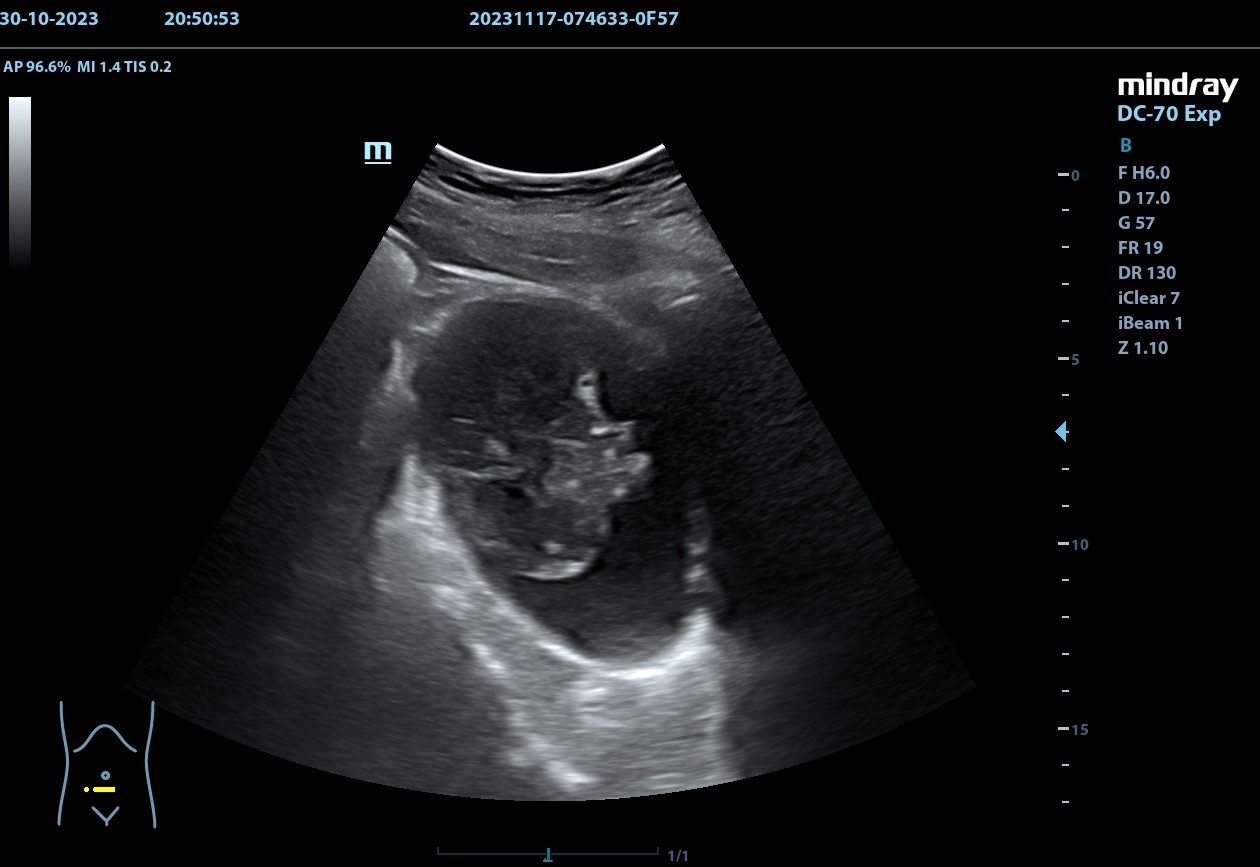

Se realiza, en consulta, una ecografía de las vías urinarias (POCUS), apreciando una lesión excrecente, pediculada, de 7,48 x 6,14 cm, que afecta a la pared izquierda y superior de la vejiga. Doppler negativo. No apreciándose jets ureterales. Riñón izquierdo de 11cm, y derecho de 9.27 cm, sin signos de dilatación de las pelvis renales que sugieran hidronefrosis.

Juicio clínico: Masa intravesical.

Diagnóstico diferencial: Tumor primario epitelial vs. tumor de origen no epitelial.